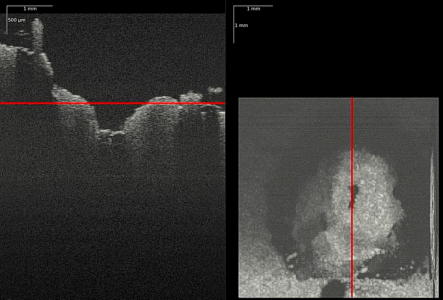

Optical Coherence Tomography (OCT) can depict deeper tissue structures, allowing surgeons visual process control. (Photo: LZH)

To prevent such injuries, researchers aim to provide surgeons with visual process control. Optical Coherence Tomography (OCT) enables the visualization of tissue layers beneath the bone. Surgeons can thus determine how much bone they can remove without hitting the meninges. The laser allows for precise bone removal with an accuracy of 10-100 μm, making it an excellent tool for creating a precise passage to the nerve canal. A combination of milling and laser removal would be possible with this therapy.